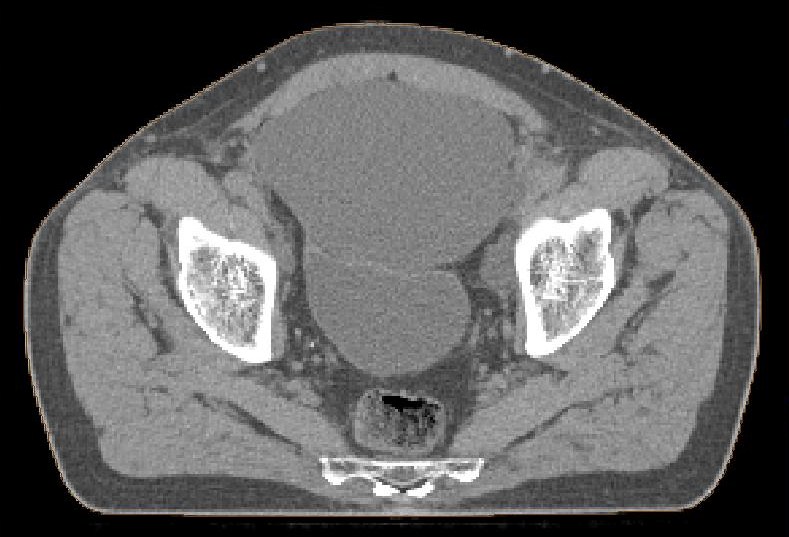

postoperative Lymphozele

Große Lymphozelen nach laparoskopischer pelviner Lymphonodektomie.